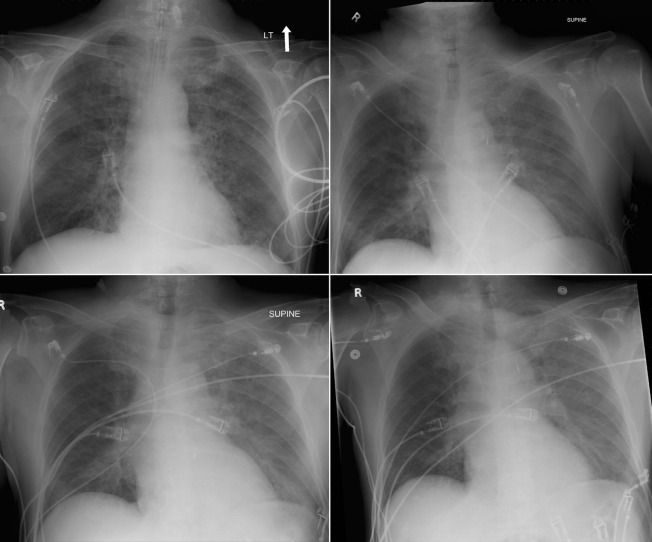

Pulsatile Devices: Intra-aortic Counterpulsation Balloon ( Figs. 24-1 to 24-7 )

The tip of an intra-aortic balloon (which is highly visible because of its metallic marker) should be at least 4 cm below the “knuckle” of the aorta (i.e., below the left subclavian artery). The balloon appears as a cylindrical lucency if the radiographic exposure happened to be while it was inflated in diastole. Widening or haziness of the aorta suggests aortic dissection as a complication of the catheter. Incorrect insertion into the inferior vena cava is suggested by the shadow of the catheter lying to the right of the patient’s vertebral column.